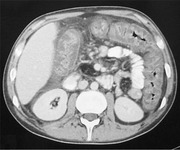

Doença associada ao Clostridium difficile: tomografia computadorizada (TC) do abdome mostrando espessamento macroscópico da parede do intestino grosso e obliteração do lúmen

Yates B, Murphy CM, et al. Pseudomembranous colitis in four patients with cystic fibrosis following lung transplantation. BMJ Case Reports. 2009; doi: 10.1136/bcr.11.2008.1218